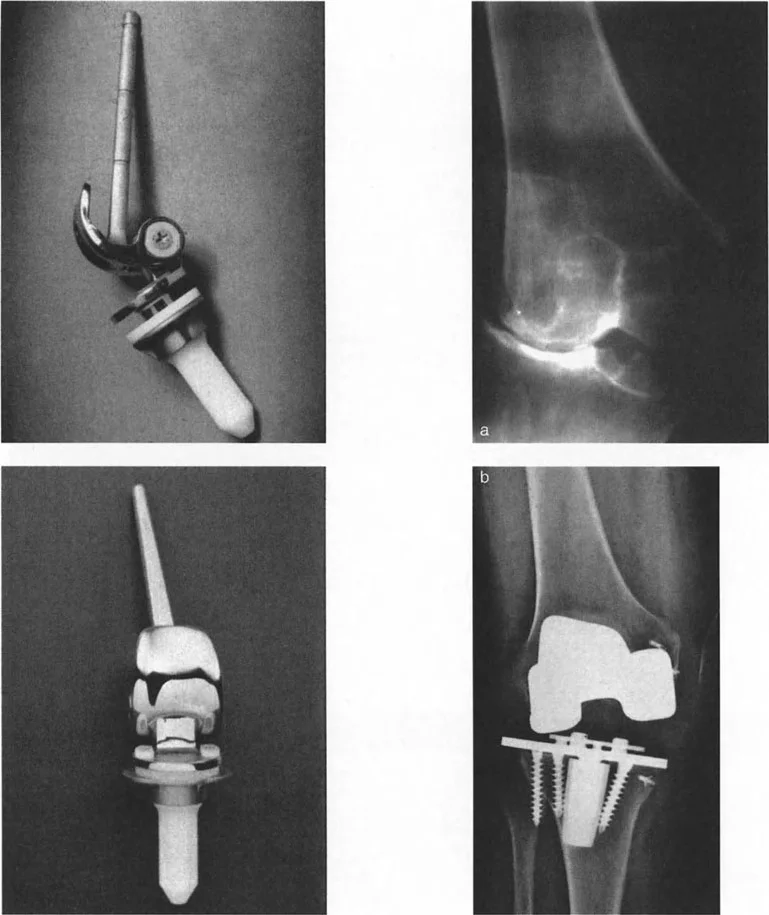

- جراحات قطع العظم وتقويم المحاور

- استبدال المفاصل في حالات التشوه الشديد

في حين أن التشوهات الديناميكية تُناقش غالبًا في سياق أمراض الأعصاب والعضلات لدى الأطفال، فإن المبادئ البيوميكانيكية التي تحكمها تنطبق عالميًا على إعادة بناء العظام لدى البالغين. يشمل ذلك سيناريوهات إعادة البناء المعقدة للغاية، مثل استبدال مفصل الركبة الكلي (TKR) واستبدال مفصل الورك الكلي (THR) المرتبطة بالانحرافات الشديدة خارج المفصل. إن فهم الأذرع الرافعة هو المتطلب الأساسي لإتقان هذه التقنيات المتقدمة في جراحة المفاصل وقطع العظم، وهو ما يتقنه الأستاذ الدكتور محمد هطيف في ممارسته اليومية.